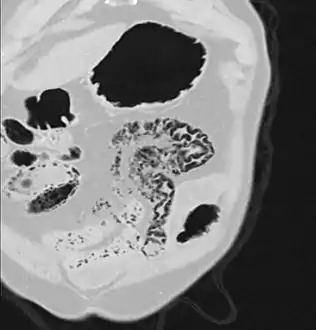

Pneumatosis intestinalis at computed tomography in intestinal ischemia. Lung window for better representation of the gas deposits in the intestinal walls. Coronal reconstruction.

Pneumatosis intestinalis in computed tomography with intestinal ischemia. Lung window for better representation of the gas deposits in the intestinal walls.